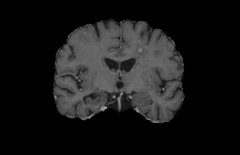

Objectives: This work aims to explore the impact of multicenter data heterogeneity on deep learning brain metastases (BM) autosegmentation performance, and assess the efficacy of an incremental transfer learning technique, namely learning without forgetting (LWF), to improve model generalizability without sharing raw data. Materials and methods: A total of six BM datasets from University Hospital Erlangen (UKER), University Hospital Zurich (USZ), Stanford, UCSF, NYU and BraTS Challenge 2023 on BM segmentation were used for this evaluation. First, the multicenter performance of a convolutional neural network (DeepMedic) for BM autosegmentation was established for exclusive single-center training and for training on pooled data, respectively. Subsequently bilateral collaboration was evaluated, where a UKER pretrained model is shared to another center for further training using transfer learning (TL) either with or without LWF. Results: For single-center training, average F1 scores of BM detection range from 0.625 (NYU) to 0.876 (UKER) on respective single-center test data. Mixed multicenter training notably improves F1 scores at Stanford and NYU, with negligible improvement at other centers. When the UKER pretrained model is applied to USZ, LWF achieves a higher average F1 score (0.839) than naive TL (0.570) and single-center training (0.688) on combined UKER and USZ test data. Naive TL improves sensitivity and contouring accuracy, but compromises precision. Conversely, LWF demonstrates commendable sensitivity, precision and contouring accuracy. When applied to Stanford, similar performance was observed. Conclusion: Data heterogeneity results in varying performance in BM autosegmentation, posing challenges to model generalizability. LWF is a promising approach to peer-to-peer privacy-preserving model training.